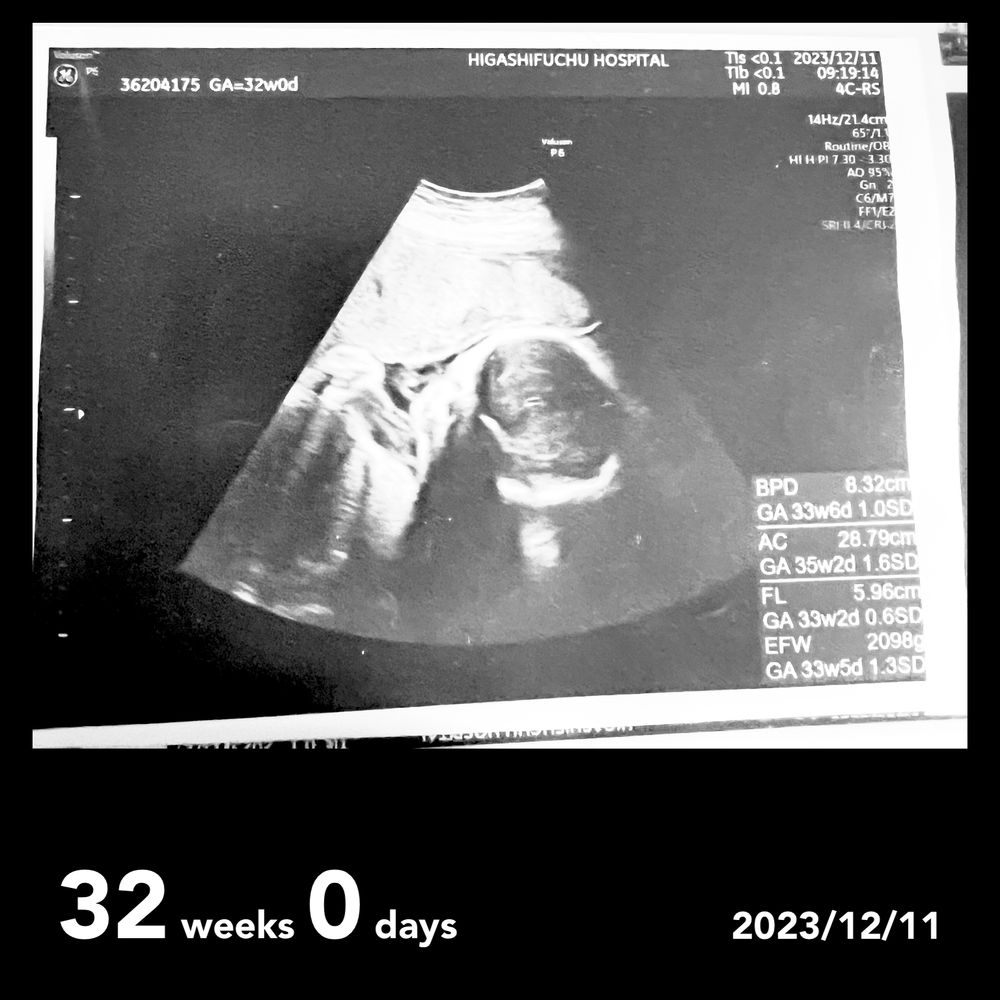

Наши неделькиВ понедельник была на приеме. Малышка по узи весит уже 2098 грамм( опережает примерно на две недели), по параметрам БПР -8,32 см( примерно срок 33 н6 дней)

ОЖ-28,79 см( срок на 35 н 2дня, то есть опережение больше чем на 2 недели)

ДБ -5,96 см( примерно 32 н 2 дня).